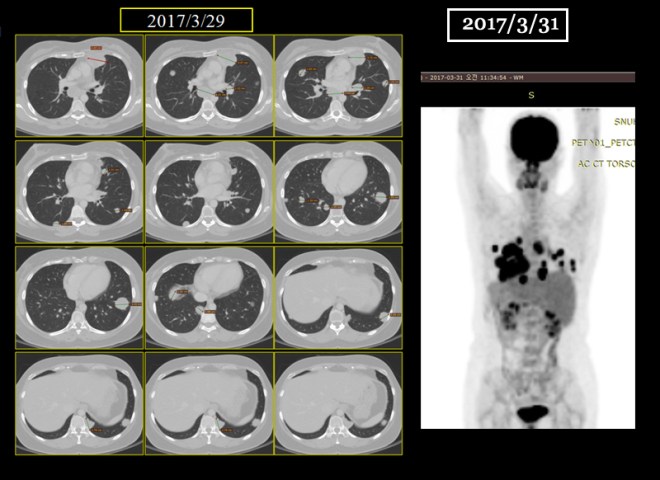

• 2017.3.29 paclitaxel #12 차 종료

• CT상 폐전이 발견. 방사선치료 예정 있었으나 폐전이 발견돼 중지

• 2017.3.31 CT chest – 다발적 폐전이와 종격동 림프절전이 발견

1-9.jpg

위에 보듯이 폐에 보이는 무수한 점들은 CT상에서는 더욱 선명하다. 다음에 PET에 나타나는 검은 점이나 CT상에서 동그란 솜 뭉쳐 놓은 것처럼 보이는 작은 원형의 점들이 모두 폐에 다발적으로 전이된 암을 표현한다.

1-10.jpg

서울대로 옮겨서 7 차 이후에 12 차까지 택솔을 시행하고 나서 종양이 매우 급속도로 폐에 전이가 되자 주치의는 약물을 바꾸어서 소음인 약물로만 구성된 gemcitabine하고 cisplatin을  2017년 3월부터 2017년 5월까지 시행하였다. 그리고 5월달 CT는 다소 종양의 감소를 보였다.

종양이 이같이 빠른 확산을 보이자 환자는 의사의 권유로 신약인 티센트릭을 사용하는 것에 동의 하였다. 티센트릭은 방광암 분야에서 현재 임상이 시도되고 있는 신약이다. 환자는 아래의 PET 사진에서 보듯이 일부는 3월에서 gemzar cisplatin이 4 차 시도되는 사이에 일부는 줄어들은 데도 있으나(원형 아래 부분) 결국은 나벨빈 사용 이후에 이같이 나빠지게 되었다.